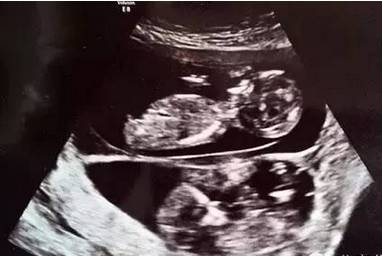

国外有位孕妈妈在怀孕期间与老公啪啪啪,结果去检查的时候发现又怀了一个,这位妈妈在第一次检查的时候,只发现一个胎儿,回家跟老公同房几次,第二次去检查的时候,发现有两个胎儿,而后面的那个胎儿已经有6周,听到这是不是觉得太不可思议了。

然而却真实的发生了,3个多月检查的时候发现这两个宝宝之间相差十几天,大小差异很大。这种在怀孕期再次怀孕的概率非常小,几乎不可能,在医学上称为异期复孕。

幸运的是整个孕期都没有什么问题,顺利生下健康的龙凤胎兄妹,看着他们好可爱。